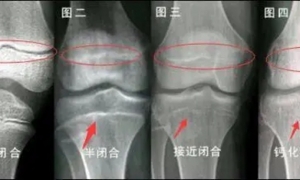

2024-09-117个方法延缓骨龄— 助力孩子身高增长—近年来,骨龄检测成为家长们关注的焦点。常有家长发现,孩子虽然看似高大,但骨龄却超前一到两岁,这究竟是何原因?是否意味着“性早熟”?事实上,骨龄超前并非直接等同于性早熟,它更多反映了骨骼发育速度相对于实际年龄的提前